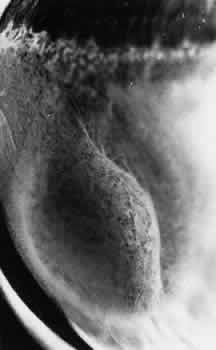

DEGENERATIVE RETINOSCHISIS

Degenerative retinoschisis, a more extensive trophic process, presents as a round or ovoid area of retinal splitting with a smooth fusiform elevation of the inner layer (Fig. 17). The schisis is surrounded on all sides by typical cystoid degeneration; the retinal pillars of the cystoid degeneration as well as the broken pillars near the margin of the schists are prominent. Vessels are located in the inner retinal layer, the intraretinal cavity is optically empty, and the outer retinal layer is moderately irregular in contour.13,14

Fig. 17. Typical degenerative retinoschisis.Note extensive region of typical cystoid degeneration with a rounded and elevated posterior margin. In the center (arrow), radial columns are randomly disrupted, causing a disturbance in coarse surface pattern. (× 18.)

In one type of degenerative retinoschisis, the thin inner wall is composed of the internal limiting membrane, the nerve fiber layer, and retinal vessels (Fig. 18). The irregular outer wall contains portions of the inner nuclear, outer plexiform, outer nuclear, external limiting, and rod and cone layers. At the margin of the cavity, the retinoschisis blends with typical cystoid degeneration and may be relatively flat. Lesions with this appearance have been termed typical degenerative retinoschisis.

Typical degenerative retinoschisis is present in 1% of adult patients and is bilateral in 33% of these patients; therefore, it is evident in 0.7% of adult eyes (see Table 3), with a predilection for location in the inferior temporal quadrant. A narrow band of typical cystoid degeneration is always present between the ora serrata and the anterior border of the schisis cavity; the involved area may extend to or somewhat posterior to the equator.